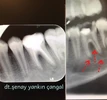

1982 yılında Trabzonda doğdu. İlk ve orta öğretimini Rize' de tamamladı. 2005 yılında Atatürk Üniversitesi Diş Hekimliği Fakültesinden mezun oldu. Aynı yıl meslek hayatına Ankara' da özel bir klinikte başlayan Diş hekimi Şenay Yankın Çangal, halen kurucu ortağı olduğu Doğal Diş Kliniğinde hastalarını kabul etmektedir. Estetik diş hekimliği, kanal tedavisi, implant ve implant üstü protetik uygulamalar odaklandığı alanlardır.

Endodonti

Lezyonlu (Enfekte) Diş